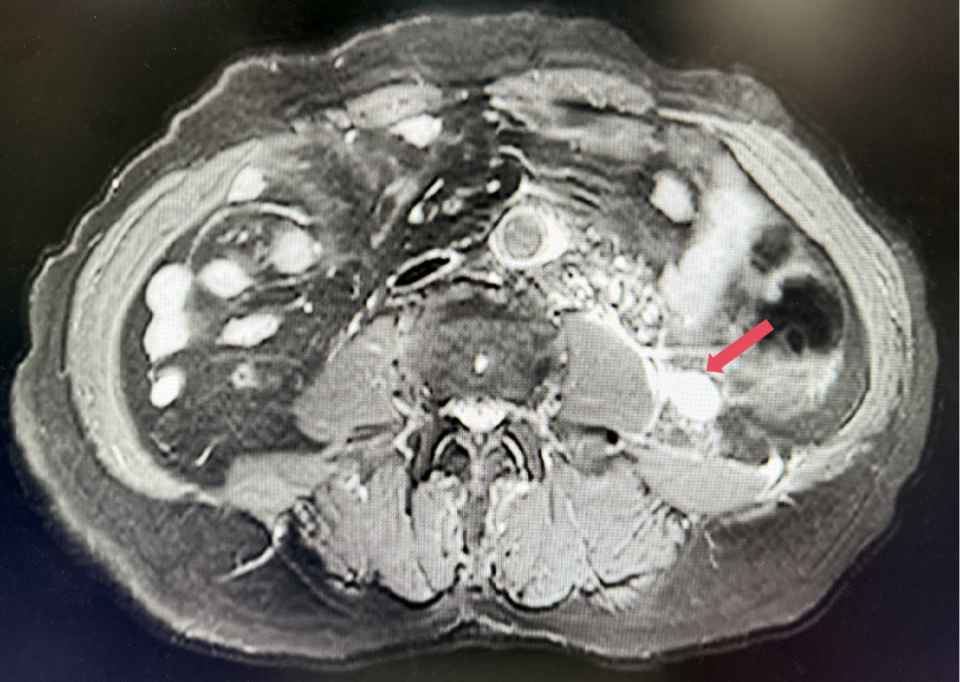

2026年4月:持续维持PR,PFS超过37个月。

2025年1月:序贯为呋喹替尼单药(5mg,po,qd,D1-14,q3w)治疗。

患者初诊时68岁,2020年9月因“体检发现左肾占位2年”行腹腔镜下左肾根治性切除术,术后病理提示为肾透明细胞癌,pT3aN0M0,未行术后辅助治疗、未规律复查。2022年3月胸腹盆CT示腹膜后转移,IMDC评分0分,低危组。随后予一线培唑帕尼治疗,最佳疗效SD,2022年11月PD。于2023年1月经筛选进入Ⅲ期FRUSICA-2临床研究,开始接受呋喹替尼联合信迪利单抗二线治疗,用药6周(C2)后首次肿评即实现疗效PR(缩瘤率40.2%),用药10个月时缩瘤率近七成(68%),并维持上述水平至今,PFS已经超过37个月,在二线治疗中实现了长期无进展生存。同时,患者对呋喹替尼联合信迪利单抗方案耐受性良好,仅见轻微蛋白尿和偶然腹泻,未见其他不良反应,也未见免疫治疗相关不良反应。该方案有望为TKI经治的晚期肾癌患者带来新的选择,为实现长期生存提供可能性。